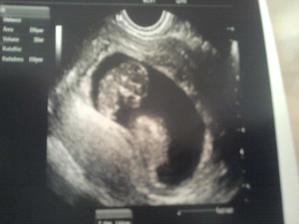

Budeme traja :o)))